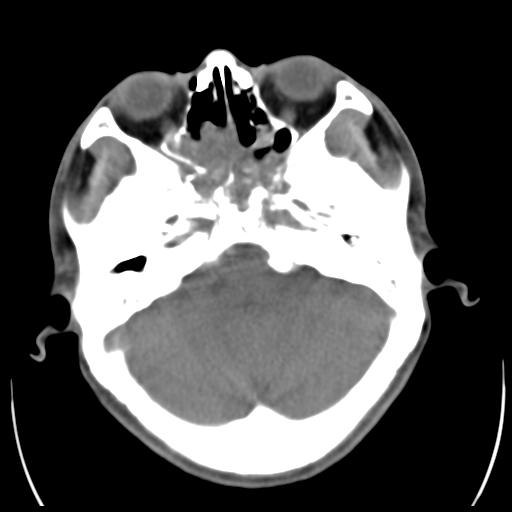

35m 鼻子时不时流血,头及右侧面部痛,颈部淋巴结未见明显大

软组织窗

考虑鼻咽癌侵犯颅底并突入右侧鼻腔;双侧中耳乳突炎。

蝶窦,后组筛窦及鼻咽部团块状软组织影,骨壁破坏,病变较广泛。考虑恶性肉芽肿。建议活检。

颅底骨质明显破坏 支持鼻咽癌 但病灶的边缘毛糙 不能除外炎性